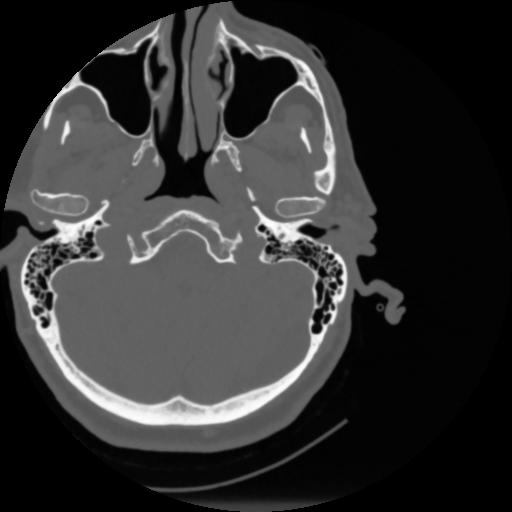

4 CEREBRO,,Vol,0.5,CEREBRO,,